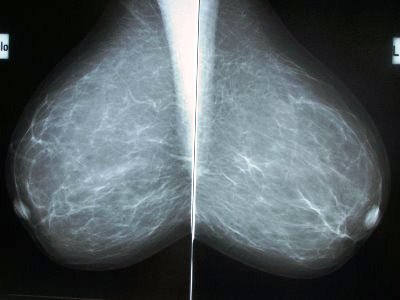

The tech knew what she was doing, effectively getting my entire breast between two pieces of Plexiglas, and squishing it like a pancake. My temporary nipple jewelry created a marker on the x-ray film. I was impressed how flat they were for the x-ray process, yet looked so full and huge looking on the film. Honestly, they looked like large goblets to hold wine in, with a jewel where the stem would begin to form.